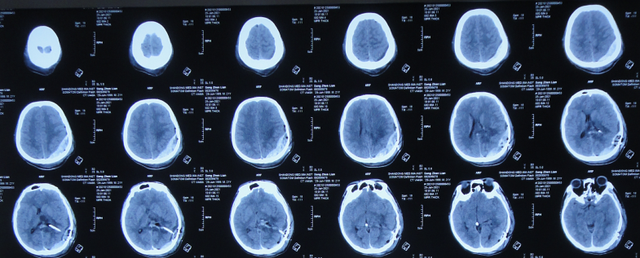

2021年3月11日(左颞角脑室腹壁外引流术后31天,脑脓肿切除术后4天),患者身体状态良好,体温变正常(图-22)。

图-22:2021年3月11日

2021年3月12日(左颞角脑室腹壁外引流术后32天,脑脓肿切除术后5天),查头颅CT示仍有少量水肿(图-23)。

图-23:2021年3月12日头颅CT

2021年3月26日(左颞角脑室腹壁外引流术后46天,脑脓肿切除术后19天),夹闭引流管1周左右,颞角没有扩张,因此进行了脑室腹壁外引流管拔除术。

但拔除引流管后11天即2021年4月6日,患者出现头痛,查头颅CT示颞角扩张(图-24)。

图-24:2021年4月6日头颅CT

因此于2021年4月8日,进行了脑室腹腔分流术;术后身体一切正常(图-25)。

图-25:2021年4月9日

于2021年4月18日(治疗近3个月)出院,出院时:身体一切正常。

三、第2次在李小勇脑脊液科治疗过程和结果

出院后5个月即2021年9月中旬,出现偶尔头痛的症状,因此于出院后7个月后即2021年11月10日,第2次来到李小勇脑脊液科;入院时:时有头痛(图-26),身体其他正常;查头颅CT示左侧颞角扩张(图-27)。

图-26:2021年11月10日入院时

图-27:入院时头颅CT

入院后2天即2021年11月12日,给予了颞角分流管调整术;术后第2天查头颅CT示颞角仍扩张(图-28)。

图-28:2021年11月14日头颅CT

入院治疗14天即2021年11月24日,查头颅CT示颞角缩小(图-29),患者头痛基本消失(图-30)。

图-29:2021年11月24日头颅CT

图-30:2021年11月24日

2022年1月4日(李小勇脑脊液科第2次治疗55天)出院。出院时:头痛已消失1月余(图-31),身体一切正常,查头颅CT示未见异常(图-32)。

图-31:2022年1月4日出院时

图-32:出院时头颅CT